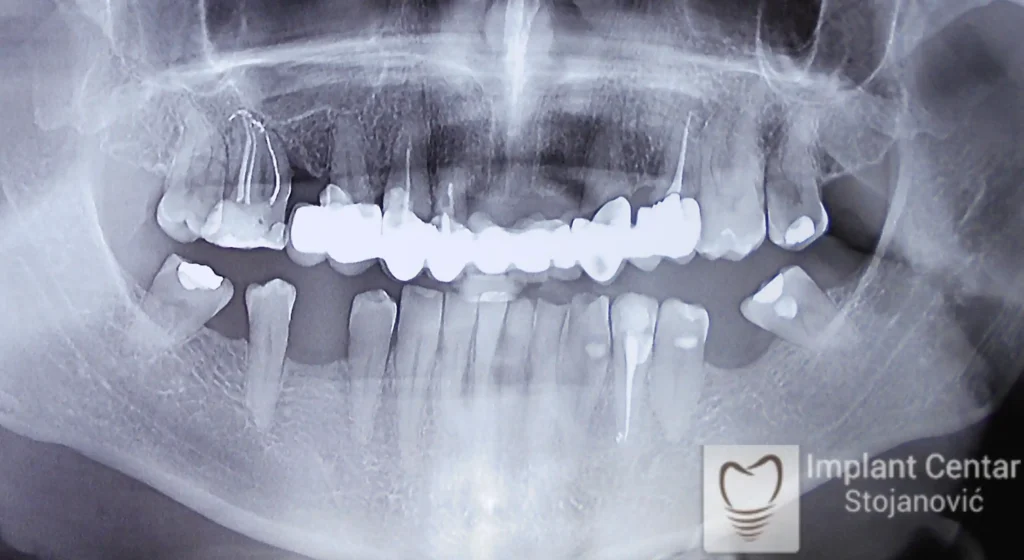

Pacijent sa rascepom usne, nepca i alveolarnog grebena uspešno je rehabilitovan fiksnim protetskim radom na implantatima. Pre dolaska u našu ordinaciju, pacijent je u gornjoj vilici nosio totalnu protezu preko preostalih zuba, dok je u donjoj vilici bio zbrinut parcijalnom mobilnom protezom. Tokom višegodišnje potrage za adekvatnim rešenjem, pacijent nije uspeo da pronađe zadovoljavajuću terapijsku opciju ni u zemlji ni u inostranstvu.

Nakon detaljnog kliničkog pregleda i analize radioloških snimaka, izrađen je sveobuhvatan plan terapije sa ciljem uklanjanja mobilnih proteza i postizanja maksimalne funkcionalne i estetske rehabilitacije. Zbog loše biološke vrednosti preostalih zuba, doneta je odluka o njihovom vađenju i ugradnji dentalnih implantata.

Poseban terapijski izazov predstavljalo je premošćavanje defekta nastalog usled rascepa, kao i ograničena količina raspoložive kosti u gornjoj vilici. Primenom većeg broja implantata i odgovarajućih procedura nadoknade kosti, postignuta je stabilna osnova za fiksni protetski rad.

Tokom perioda oseointegracije, pacijent je bio zbrinut fiksnim privremenim krunicama, čime je već pet dana nakon intervencije obezbeđena potpuna funkcionalna i estetska rehabilitacija. Nakon završetka perioda integracije implantata, izrađeni su definitivni cirkonijum-keramički mostovi na implantatima.